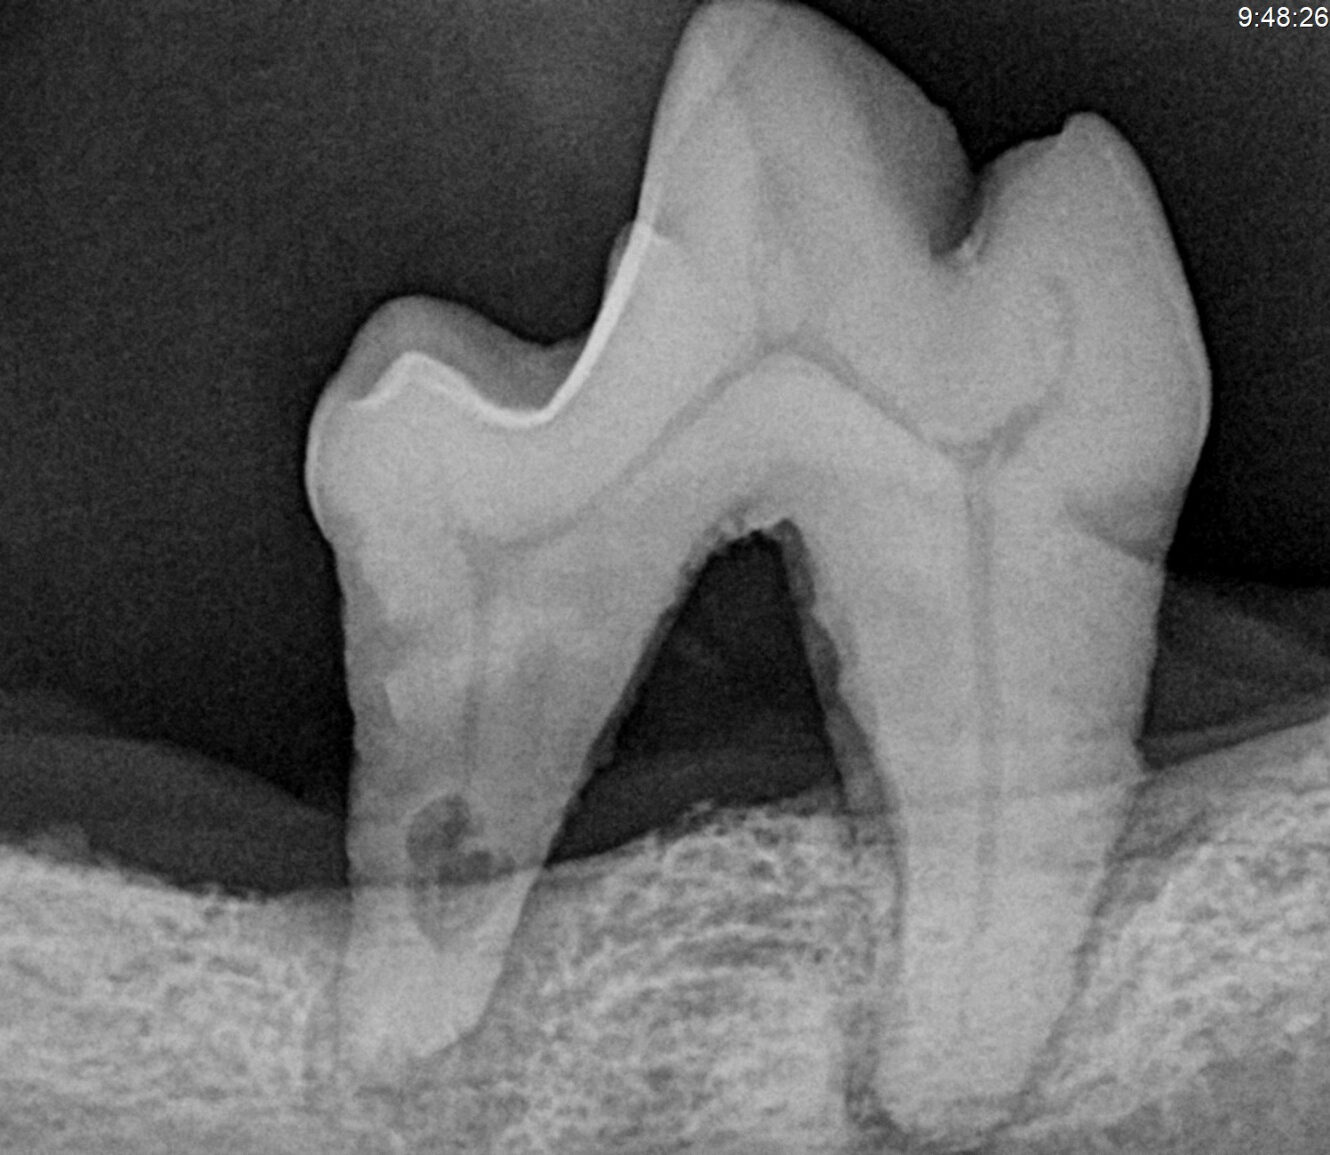

Realizamos una evaluación clínica completa de la cavidad oral desde la comodidad de tu casa para identificar problemas como acumulación de sarro, gingivitis, enfermedad periodontal, fracturas dentales y mal aliento persistente.

- Evaluación clínica dental.